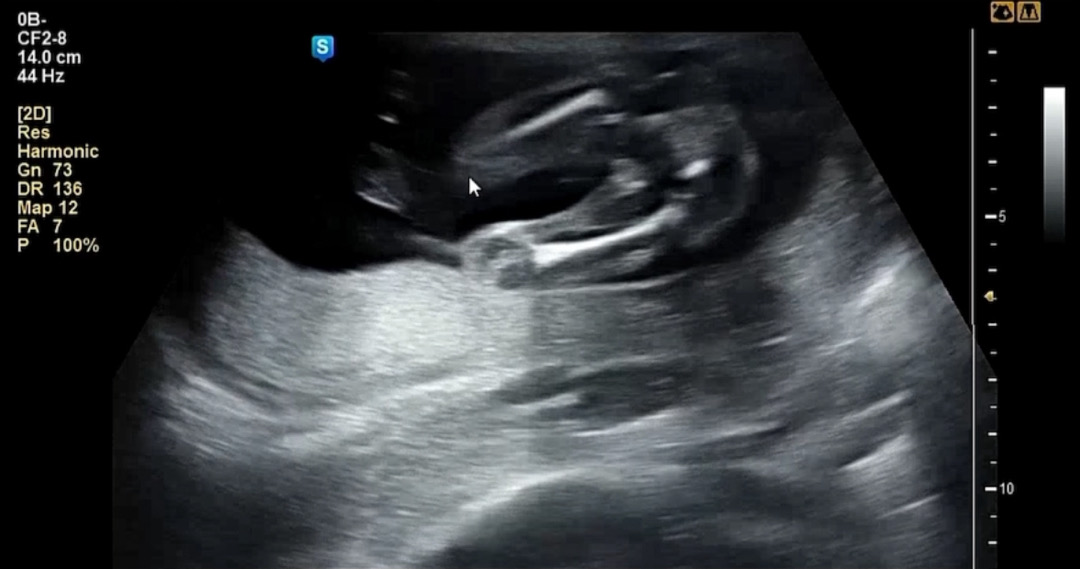

이정도면 딸확정인가요?

병원은 원래 확답을 안주시나요 19주차인데 ㅋㅋㅋㅋㅋㅋ제가보기엔 너무나딸같아서요 반전이있을까요

딸같아요 :) 첫째때 14주쯤 숨겨서 안보였던 게 16주차에 존재감 뿜뿜이었거든요 ㅋㅋ 아들이면 너무도 확실...

저 14주차때 아들 확정받았는데 아들은 존재감 뿜뿜해요ㅋㅋ 매끄러운거 보니 딸같아요ㅎㅎ

저는 15주에 아들확정 받았는데 완전 딸이에욬ㅋㅋㅋㅋㅋㅋ 아들은 누가봐도 아들이더라구요😁

딸같은데용? 첫찌둘찌두 저렇게 매끈햇오용